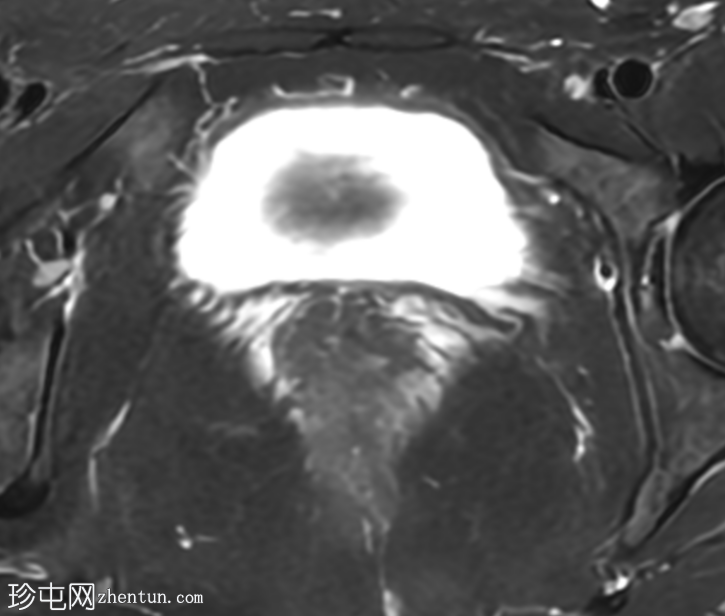

轴位T1加权像

增强脂肪抑制像

盆腔MRI显示右侧卵巢解剖位置可见一边界清晰的卵圆形肿块。该病灶由囊性和实性成分组成。囊性部分壁薄,在T2加权像上呈均匀高信号,在T1加权脂肪抑制序列上呈低信号,无对比剂增强。该实性成分的信号特征与正常卵巢组织相似,DWI成像未见扩散受限,静脉注射造影剂后未见异常强化。

此外,在子宫左侧壁可见一管状薄壁囊性结构,延伸至同侧髂外血管,末端呈盲端。该结构在T2加权像上呈均匀高信号,在T1加权脂肪抑制序列上呈低信号,且无造影剂强化。

本例中,盆腔MRI显示,患者右侧卵巢解剖位置存在一个边界清晰的附件肿块,该患者有20年前行双侧输卵管卵巢切除术的病史。该病灶包含囊性和实性成分,其中实性部分表现出与正常卵巢组织相似的信号特征。无扩散受限和无可疑的增强扫描强化提示排除恶性病变。这些影像学特征结合相关的手术史进行解读,符合残留卵巢组织的特征,支持卵巢残留综合征的诊断。此外,还发现对侧子宫左侧延伸出一个管状薄壁囊性结构,末端呈盲端。其形态、信号特征和无强化表现符合输卵管残端或输卵管残端积水,这是输卵管切除术后常见的术后表现。附件残余的存在进一步支持术后病因,而非原发性妇科肿瘤

主要鉴别诊断包括腹膜包涵囊肿、子宫内膜异位症相关囊肿和附件肿瘤。腹膜包涵囊肿通常位于腹膜腔内,不含类似卵巢组织的实性成分。子宫内膜异位囊肿通常在T1加权像上表现为高信号,T2加权像上出现阴影,并具有其他特征性MRI表现,而本例4中均未见这些表现。鉴于无扩散受限、无可疑强化以及实性成分的良性影像学表现,肿瘤性病变的可能性较小。